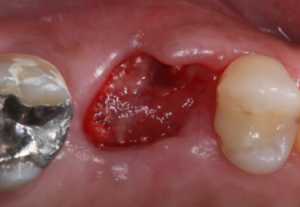

Vista oclusal do elemento16 pós-exodontia. Notar que a tábua vestibular foi reabsorvida.

Vista oclusal do elemento16 pós-instrumentação.